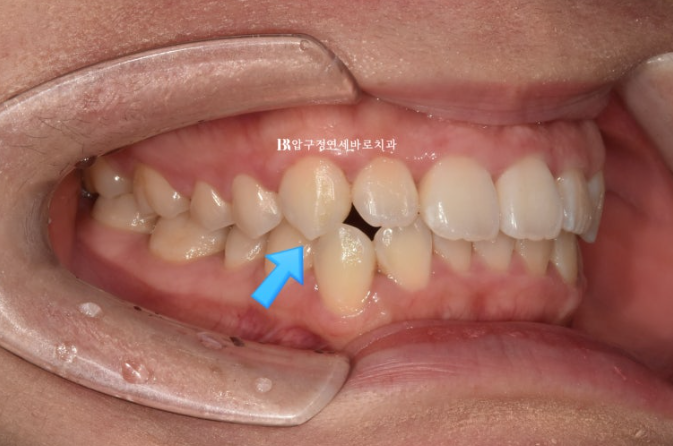

23.07

파란 화살표는 송곳니끼리 거꾸로 물리는 반대교합도 보입니다.

앞니가 삐뚤하고 아래 악궁 모양이 둥글지 않고 네모진 형태입니다.

어금니 교합은 좋았기에 인비절라인 라이트로 교정치료 권유드렸습니다.